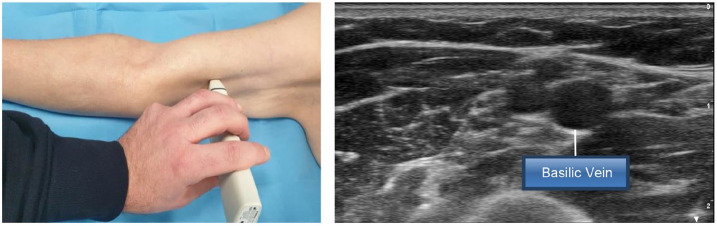

外周置入中心导管(PICC)的插入可能会带来直接/早期不良事件的风险,其中有些风险很小(重复穿刺),有些则很严重(意外动脉穿刺或神经相关损伤)。在插入过程中采取的几种策略可将此类事件的风险降至最低,包括感染、静脉血栓或导管脱落和/或错位等后期并发症风险。本文介绍了 SIP 协议(PICC 安全插入)的更新版本,该插入捆绑包包括八种有效策略,旨在最大限度地减少与插入相关的即时、早期或晚期并发症。这些策略包括:利用 RaPeVA(快速外周静脉评估)方案进行术前超声评估;适当的皮肤消毒技术;选择适当的静脉,采用 Zone Insertion Method™(区域插入法);明确识别正中神经和肱动脉;超声引导下穿刺;超声引导下的尖端导航;术中评估尖端位置;正确固定导管以及适当保护出口部位。这一更新版 SIP 方案包括几项基于 PICC 插入最新循证科学文献的新技术,如隧道技术的临床实用性、术中尖端导航和尖端位置超声的使用,以及出口部位保护(氰基丙烯酸酯胶)和导管固定(皮下固定)的新技术。

Insertion of Peripherally Inserted Central Catheters (PICCs) is potentially associated with the risk of immediate/early adverse events, some of them minimal (repeated punctures) and some relevant (accidental arterial puncture or nerve-related injury). Several strategies adopted during the insertion process may minimize the risk of such events, including late complication risks such as infection, venous thrombosis, or catheter dislodgment and/or malposition. This paper describes an update version of the SIP protocol (Safe Insertion of PICCs), an insertion bundle which includes eight effective strategies that aims to minimize immediate, early, or late insertion-associated complications. These strategies include: preprocedural ultrasound assessment utilizing the RaPeVA (Rapid Peripheral Venous Assessment) protocol; appropriate skin antiseptic technique; choice of appropriate vein, adoption of the Zone Insertion Method™; clear identification of the median nerve and brachial artery; ultrasound-guided puncture; ultrasound-guided tip navigation; intra-procedural assessment of tip location; correct securement of the catheter, and appropriate protection of the exit site. This updated version of the SIP protocol includes several novelties based on the most recent evidence-based scientific literature on PICC insertion, such as the clinical relevance of the tunneling technique, the use of ultrasound for intra-procedural tip navigation and tip location, and the new technologies for the protection of the exit site (cyanoacrylate glue) and for the securement of the catheter (subcutaneous anchorage).